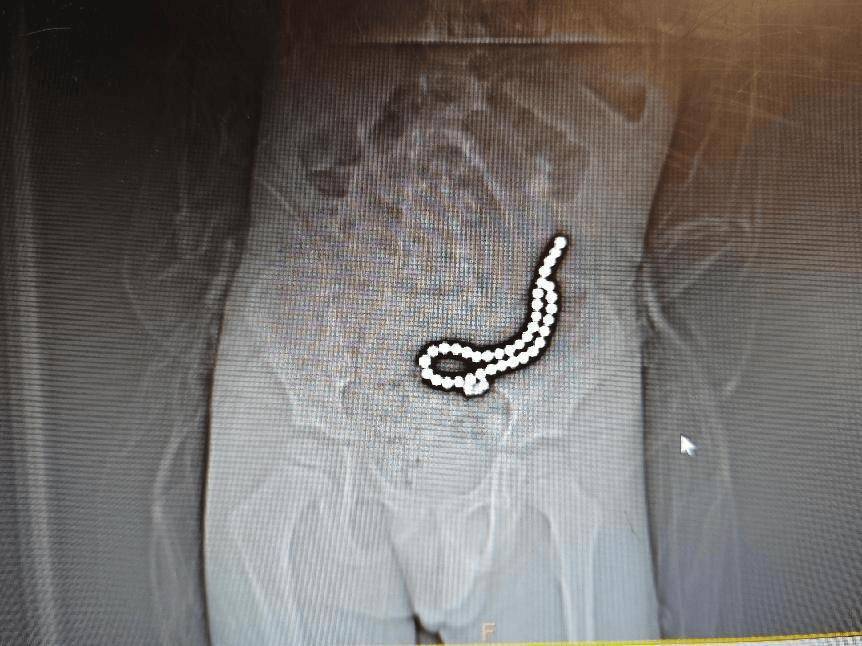

经过初步的影像学检查,医疗团队发现:病人体内竟然有37颗异物,连在一起呈手串状,并伴有小肠穿孔拜仁慕尼黑足球 。

术前腹部DR片